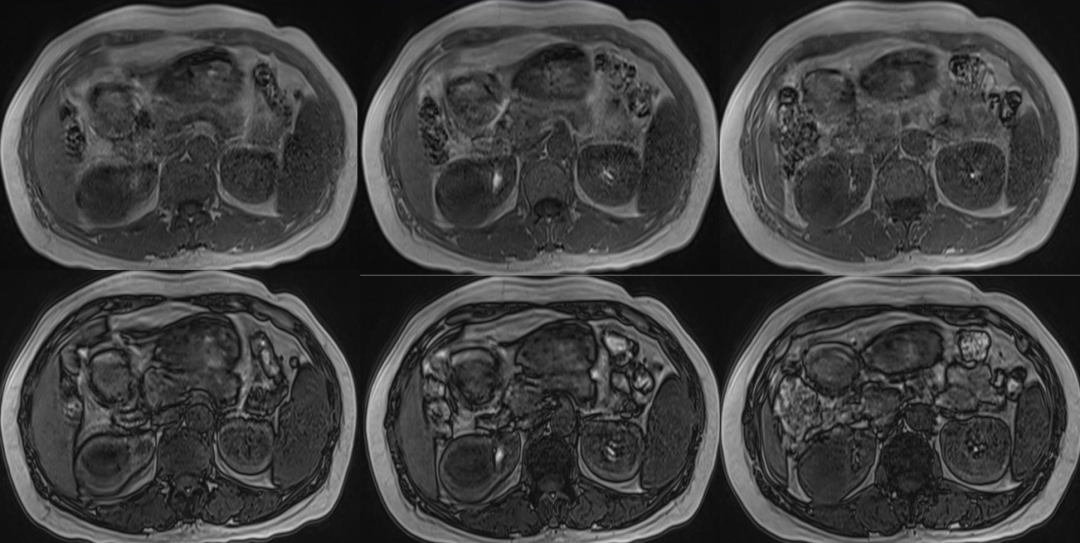

"熊掌征"(bear paw sign)是指在断面影像上肾盂粘连收缩,而肾盏扩张,肾皮质变薄,扩张的肾盏形似熊脚掌的征象,它是黄色肉芽肿性肾盂肾炎的一个重要特征性征象。

"熊掌征"表现为以肾盂肾盏为中心肾实质内多发囊性占位,其中部分囊为结石梗阻所致的肾积水,部分为黄色肉芽肿的脓腔;通常肾盏扩张为主,肾盂扩张常常不显,增强后,病变实性部分均匀强化,坏死区无强化,低密度区边缘环形强化。患肾体积增大或局限性隆起。常常伴有集合系统结石;肾皮质变薄;肾窦脂肪组织减少,多为慢性炎性反应性纤维组织增生所替代;肾周筋膜增厚、肾周间隙渗出积液,严重时可形成脓肿累及腰大肌。腹部X线平片典型的表现是受累的肾脏增大并有鹿角状结石,同侧腰大肌边缘模糊。超声显示肾脏轮廓变形,正常结构消失,中央可探及结石声影。

"熊掌征"主要见于黄色肉芽肿性肾盂肾炎(XGP)。本病在任何年龄均可发病,但以50~70岁多见;女性患者明显多于男性。一般仅有单侧肾脏受累,罕有双侧病变;绝大多数患者肾区疼痛及反复发作的